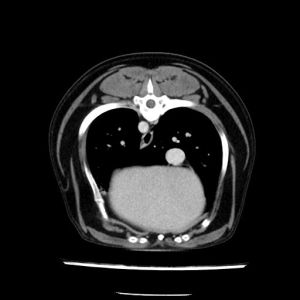

La lesione focale epatica , la ceus,la Tac e il chirurgo .